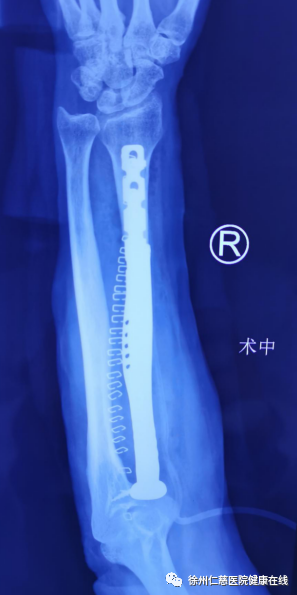

据了解,定制假体工程师团队对于这样棘手的病例,目前也只是全国第二例,而且第一例骨肿瘤的节段远小于本次病例,对他们来讲,挑战也很大;所以在术前,手术医生及定制假体工程师团队获取了患者骨骼的精确数据后,还进行了反复多次的探讨和商定,才为患者设计出与骨骼完全匹配的定制3D人工假体,为了增加假体的稳定性,辅助设计了钢板来支撑稳定,完善个性化和精细化的准备。

经过详尽的术前准备,预演了各种可能的细节,确保万无一失后,sararz关节科出动了最强“天团”,张传开主任和邱东新副主任医师在台上“把刀”,张贯林副院长和蒋守海主任台下“护航”,在手术室和麻醉科的通力合作下,手术医生小心翼翼地分离和保护重要的神经、血管,既完整彻底切除桡骨肿瘤,同时也最大限度地保留正常的组织和结构;然后再进行精细的骨骼重建程序,对假体放置的位置、角度进行了精细化调整,各组肌腱韧带给与充分的重建,恢复正常的生理功能,以保证术后患肢的功能得到最大程度的保留。

“肿瘤活检及免疫组化结果显示低度恶性,这一次术后患者还需要再一次进行骨肿瘤的病理检查复核,根据结果来指导后续的治疗。目前手术非常成功,患者术后肢体功能没有任何丧失;术前患肢旋后功能只有40°,术后肢体功能可以达到正常的90°,甚至比术前效果更好。后期只要配合好康复锻炼,功能恢复完全没有问题。”邱东新医生说。